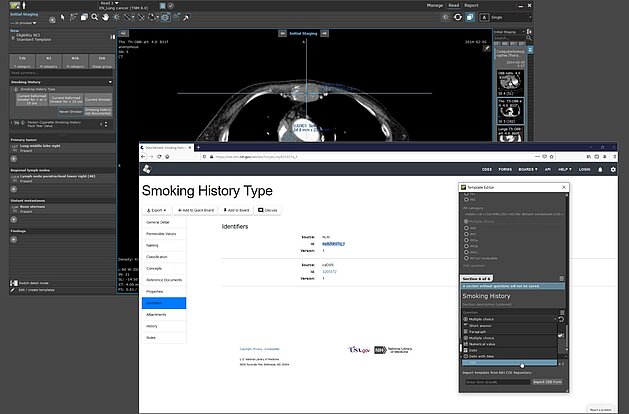

Today, it is generally agreed that standardized language used in radiology reports improves communication with the treatment team and patients, with a…